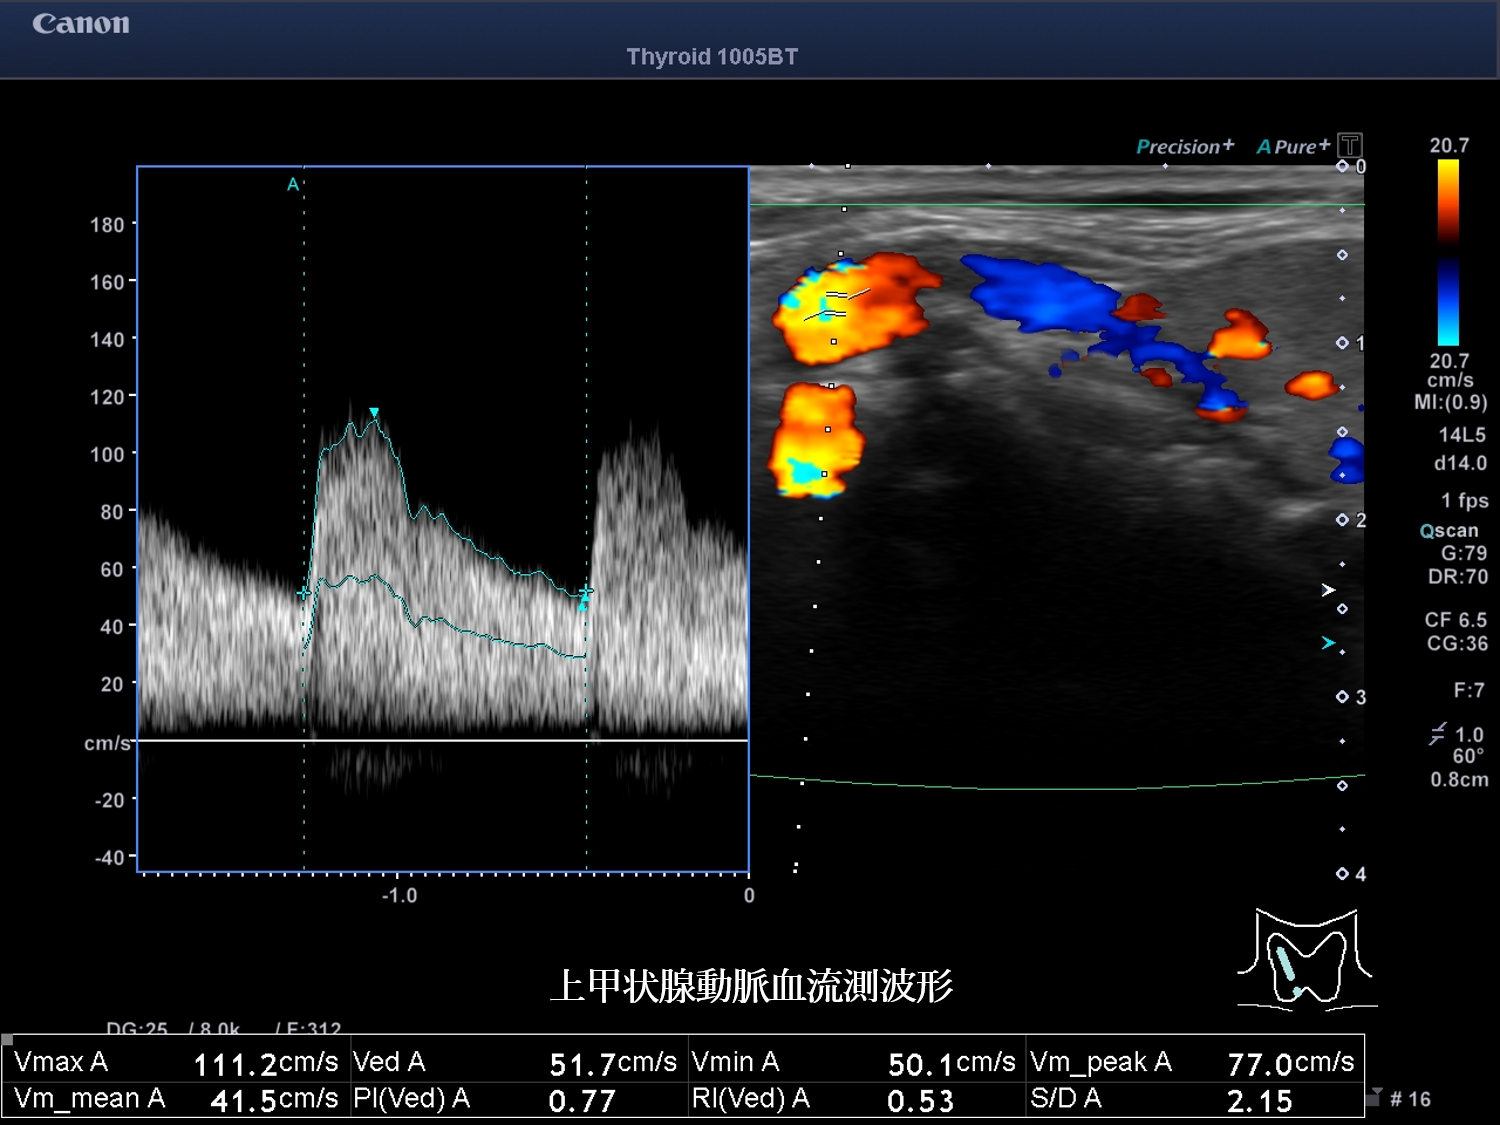

甲状腺超音波 動画 右葉横断像 カラー(No20-21_A)